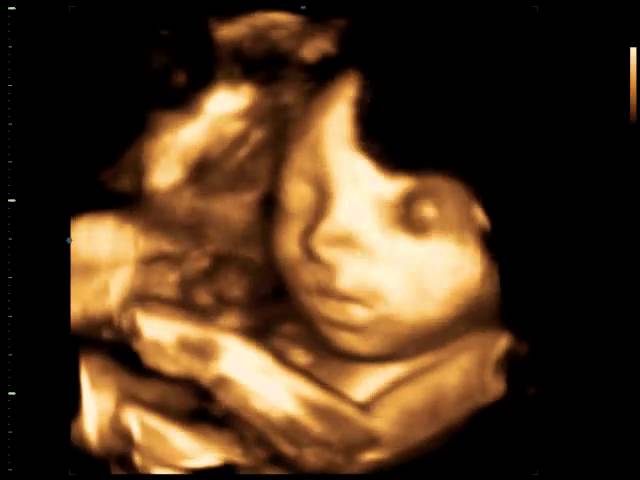

Ambas mostram detalhes do bebê, tais como contornos e fisionomias. A 4D permite ver o bebê em movimento, sorrindo, bocejando, passando a mão no rosto, abrindo e fechando as mãos entre outras peripécias.

Esta modalidade de ecografia gera imagens do bebê que são armazenadas em DVDs. Desta forma, nos parece mágico mostrar para seu filho, no futuro, como ele se comportava na barriga da mamãe.

Atualmente, disponibilizamos de tecnologia capaz de oferecer imagens tão reais dos bebês que podemos dizer com quem eles se parecem mesmo antes de nascerem. Podemos acompanhar com detalhes cada passo da formação de uma nova vida.